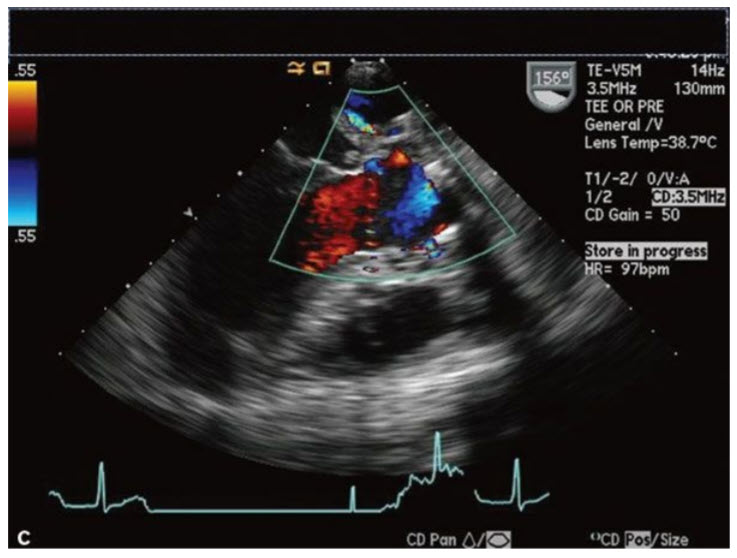

The images in Figures below A–C are from a 43-year-old s/p carpentier edwards aortic valve replacement (CE AVR) with fevers and night sweats.

These images demonstrate all of the following except:

Aortic insufficiency (AI). Although all of the answers are possible complications of infective endocarditis, the images displayed in Figures in question do not show any significant AI. Figure A in question shows the short axis of a bioprosthetic AV with a paravalvular abscess with vegetations. It also shows the valve during systole which although it is open, the opening is restricted suggestive of AS which is confirmed by the peak AV gradient of 92.6 mmHg shown in Figure B in question. Figure C in question shows the long-axis TEE view of the AV with a small fistula into the LA (seen at the top of the image).